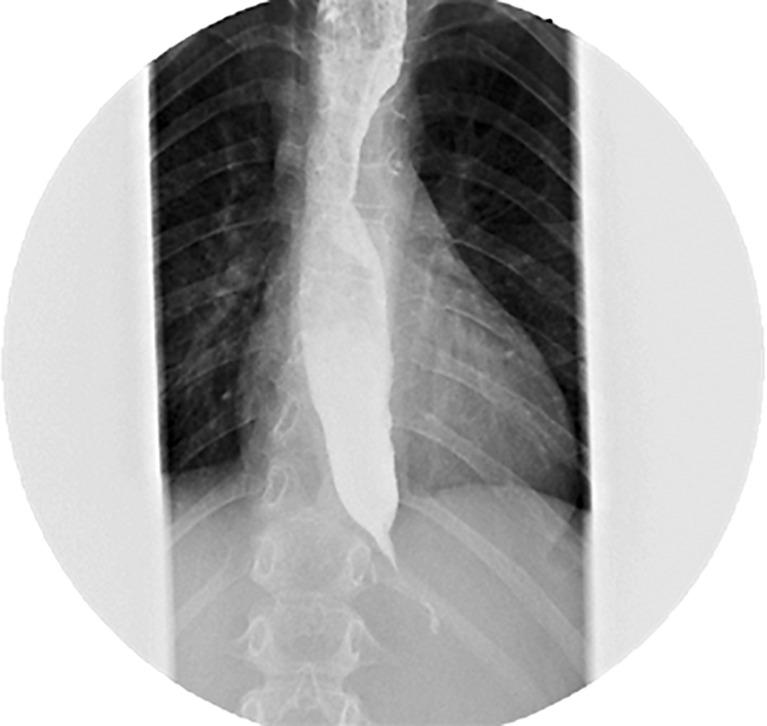

We present the case of a female child born in 2013, without relevant family history or perinatal events. At 6 years old, she presented with seizures related to recurrent hypoglycemia episodes, and adrenal insufficiency was diagnosed. Two years later, the patient was referred to our institution due to regurgitation and vomiting, causing failure to thrive. After an upper endoscopy with no significant findings, high-resolution manometry revealed type II achalasia. Alacrima was also part of the clinical picture, and Allgrove syndrome was genetically confirmed. Due to significant symptoms, an endoscopic pneumatic dilation was performed, with transient relief of symptoms. After a second pneumatic dilation and several hospitalizations due to achalasia complications, a POEM was considered. She underwent POEM in March 2024, without adverse events and excellent short-term outcomes.

我们报告一例2013年出生的女童病例,无相关家族史或围产期事件。6岁时,她因反复低血糖发作出现癫痫发作,被诊断为肾上腺功能不全。两年后,患者因反流和呕吐导致发育不良转诊至我院。上消化道内镜检查未发现明显异常,高分辨率测压显示为Ⅱ型贲门失弛缓症。无泪也是临床表现之一,经基因检测确诊为奥尔格罗夫综合征。由于症状严重,进行了内镜下气囊扩张术,症状得到短暂缓解。在第二次气囊扩张术及因贲门失弛缓症并发症多次住院后,考虑进行POEM。她于2024年3月接受了POEM手术,无不良事件发生,短期效果良好。